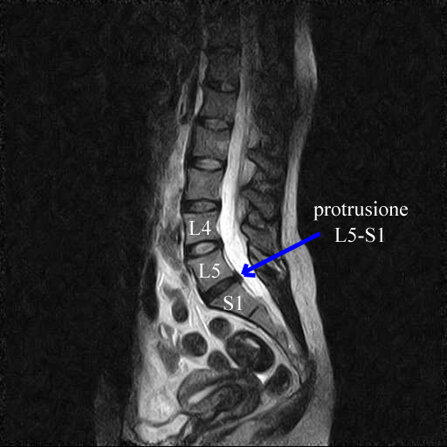

Non vi è generalmente proporzione tra l’entità del quadro radiologico (alterazioni rilevate alla tac e/o alla risonanza magnetica) e lo stato clinico e relativa sofferenza del paziente.

Può essere invece proposta la combinazione dell’ozono-terapia ecoguidata, con azione anti-infiammatoria e antidolorifica locale sulla patologia degenerativa (potenziata notevolmente dall’ecoguida, ossia dalla possibilità, mediante il contemporaneo utilizzo di un ecografo, di indirizzare con precisione l’ozono alle vertebre e ai dischi degenerati) e della scrambler therapy, capace di sostituire lo stimolo nocicettivo con uno nuovo stimolo favorevole al cervello.